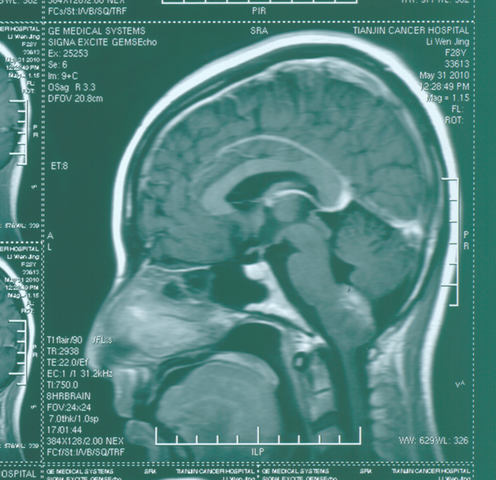

胶质瘤:

手术后